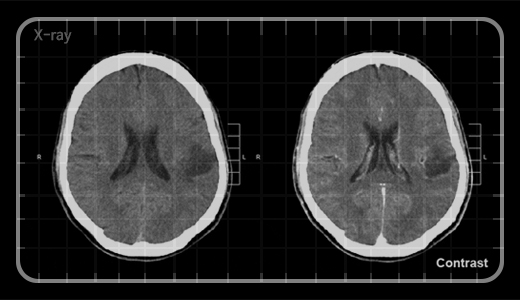

이분께서는 뇌종양 말기로 가운데 위치한 원뇌실이 나비 모양이어야 하는데 반이 이미 6개월 만에 암으로 잠식된 모습이 보입니다. 암이 커지면 어떻게 될까요? 뇌압이 높아져 계속 구토를 하게 되고, 머리가 깨질 듯이 아픈 두통, 그리고 뇌전증 발작이 나타납니다. 또한, 뇌압을 낮추기 위해 복용한 스테로이드제의 부작용으로 피부 염증, moon face 등과 같이 살이 찌기도 하지요. 병원에서는 3개월도 못 사실 거라고 하신 분이었어요.

그런데 한약을 꾸준히 먹고 나서 스테로이드 복용 중지하시고 정상 체중으로 정상 활동하시고 계십니다. 한약 치료 36개월 이후 만에요. 병원 가서 다시 사진을 찍어 보내주신 걸 보니 오히려 뇌종양은 더 자라서 둥글던 모양도 쭈글쭈글해지고, 중간에 괴사한 부분도 보이더군요. 환자의 실제 상태는 호전되어 지속적 생존이 가능한 상태인데도요. BBB에 의해 약물이 뇌까지 침투되지 않아 참 치료하기 어려운 게 뇌인데 그나마 한약이 침투되어 무엇인가 작용을 한 것이겠지요.